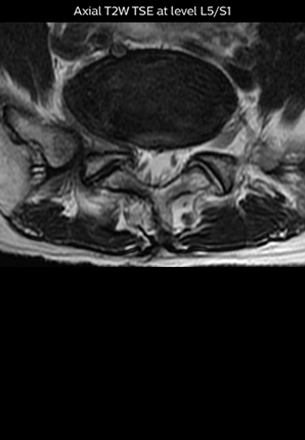

At Northern Fukushima Medical Center in Japan, excellent MRI visualization of nerves helps support confident diagnoses and informs surgical treatment decisions for patients with lower limb symptoms. MRI technologist Tanji and orthopedic surgeon Dr. Yabuki share how direct nerve visualization with the 3D NerveVIEW method adds information when diagnosing atypical herniations. The additional insights changed their way of working and benefit their patient care, as illustrated by some clinical examples.

“In patients with lower extremity neurological symptoms, NerveVIEW helps us to determine the disease matching the patient’s symptoms by directly visualizing the nerves. We use the sequence mainly, when there is suspicion of intraforaminal stenosis, extraforaminal stenosis or lateral disc herniation, which is often based on routine T2- and T1-weighted images. Additionally, the excellent depiction of the course of nerves makes NerveVIEW a good navigator when applying treatment such as block therapy or surgery.”

The key concept in MR neurography, Dr. Yabuki stresses, is the ability to directly visualize spinal nerves, versus inferring the presence of pathology indirectly. “Before NerveVIEW, we estimated compression of the nerve by looking for the presence or absence of fat signal on other MR images,” he says.

“For example, in sagittal images, when the presence of fat is observed in the intervertebral foramen, it suggests that there is a margin around the nerve. Similarly, the absence of fat indicates that the nerve is being compressed. So, we used to deduce nerve compression indirectly. With NerveVIEW, however, we can observe the condition of the nerves directly, regardless of the presence or absence of fat. We always prefer such direct observation of anatomy over having to make an inference about it.”

“Although symptoms of typical disc herniation and atypical hernia are very similar, the actual site of herniation is different. It is therefore important to characterize the nerve’s condition both inside and outside of the intervertebral foramina. “Conversely, if we see no abnormality in NerveVIEW, we can assume at least that there is no severe condition that requires surgery. Like this, it can help us avoid unnecessary surgery. NerveVIEW can have a tremendous impact in this way.”

“NerveVIEW is really useful for those cases where a nerve disorder is strongly suspected based on the clinical examination but our regular MRI images do not show any findings. These atypical herniations and spinal canal stenosis, occurring in 5% to 15% of the total lumbar herniation/stenosis cases are our main target when using NerveVIEW,” says Dr. Yabuki.